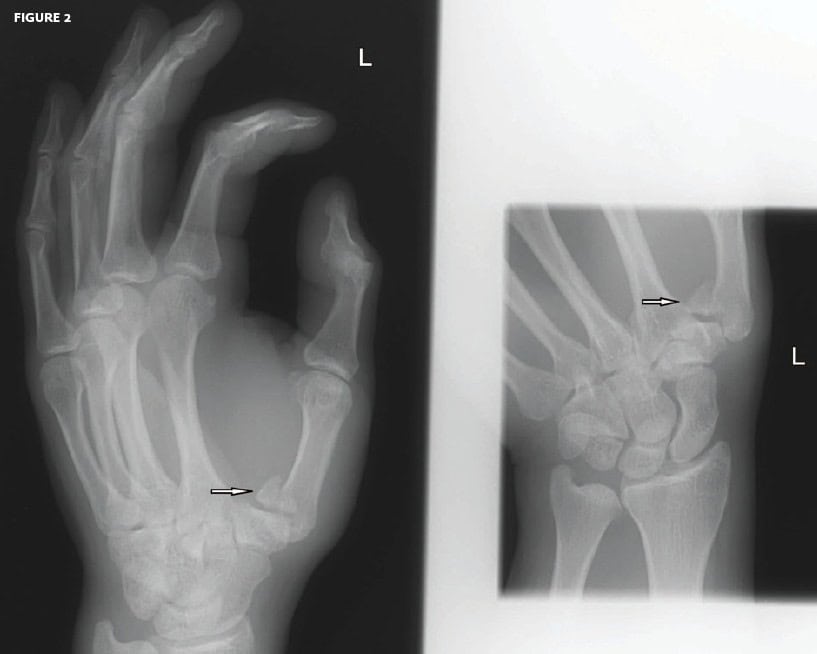

Diagnosis: The x-rays reveal a Bennett fracture (arrows).

Bennett fractures are caused by an axial loading of a flexing thumb, often from a fall or blow from an object like a soccer ball or football. Closed reduction and thumb spica immobilization are indicated, but these injuries frequently re-displace and should always be managed in consultation with an orthopedic surgeon. Open reduction and fixation for persistent displacement is required.